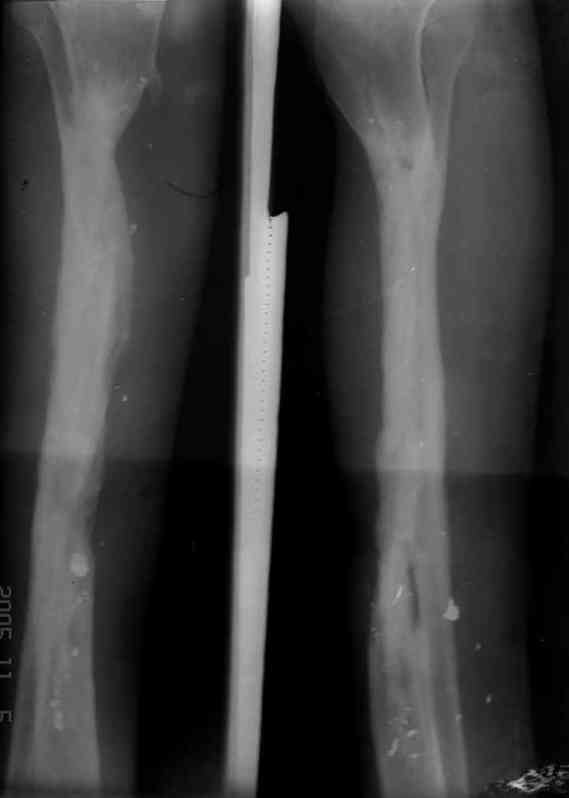

Пациент 19 лет, производственная травма, придавлен тяжелой плитой. Политравма (ISS 21).

1 - рентгенограмма (прошу прощения за качество) при поступлении;

2 - внешний вид голени;

Произведено ПХО, acute shortening (5 см), фиксация стержневым аппаратом Hoffman.

3,4 - через 4 недели наложен спице-стержневой аппарат, произведена остеотомия большеберцовой кости в верхней трети, раны зажили, проводилась дистракция в аппарате.

5, 6 - через 2,5 мес после травмы выполнен закрытый остеосинтез блокируемым штифтом.

7, 8, 9, 10, 11 - через 8 мес после травмы перелом сросся.

Пациент ходит без дополнительной опоры, не хромает (видеоролик выложил сюда

http://rapidshare.com/files/14134274/Patient_B.AVI.html, вес 892 кб).